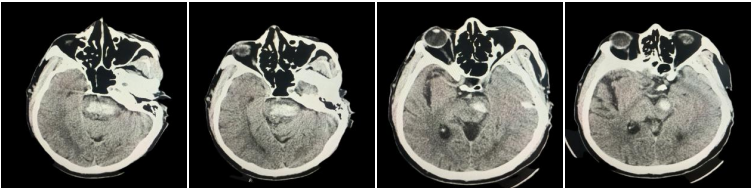

近日,我院成功救治一名 54 岁突发脑干出血患者。该患者因「突发意识不清 2 小时」被紧急送至我院,急诊科团队迅速启动卒中绿色通道,经头颅 CT 检查,确诊为脑干出血约 3 ml。由于脑干位置特殊、功能关键,脑干出血被称为神经外科的「手术禁区」,治疗过程中每一步都关乎生死。

在积极控制血压、给予止血药物治疗后,患者复查头颅 CT 显示出血量增加至 7 ml,病情进一步加重。医疗团队综合评估认为,脑干区域手术风险极高,经与家属充分沟通,最终决定实施个体化保守治疗方案。同时,医院立即组织呼吸科、麻醉科等多学科专家进行联合会诊,共同制定精准、系统的救治策略。